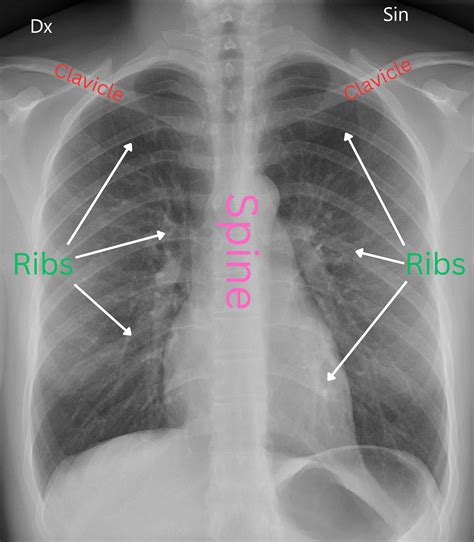

Radiología

La radiografía de tórax en las fases agudas puede ser normal o presentar infiltrados pulmonares difusos. En las fases crónicas podemos observar un patrón reticular bilateral.

En la TCAR torácica, en las fases agudas, es característica la presencia de infiltrados difusos en vidrio deslustrado y las imágenes hiperlucentes (estas como consecuencia de bronquiolitis concomitante), que en conjunto proporcionan una imagen de perfusión en mosaico. Es también típica la existencia de nódulos centrolobulillares en algunas de las fases de la enfermedad, pero son más frecuentes en las fases agudas (fig. 3A). En las formas crónicas destaca la presencia de imágenes en forma de panal. En un 20% de los casos de EPG se puede objetivar la presencia de enfisema en pacientes no fumadores.

La distribución de la afectación es típica en campos medios y superiores, aunque la presencia en campos inferiores no es excluyente, lo que hace en ocasiones que sea de afectación predominantemente en panal y que la imagen de la TC sea indistinguible de un patrón radiológico de neumonía intersticial usual (NIU) (fig. 3B).